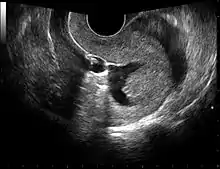

Gynecologic ultrasonography or gynecologic sonography refers to the application of medical ultrasonography to the female pelvic organs (specifically the uterus, the ovaries, and the fallopian tubes) as well as the bladder, the adnexa, and the recto-uterine pouch. The procedure may lead to other medically relevant findings in the pelvis.This technique is useful to detect myomas or mullerian malformations.

The examination can be performed by transabdominal ultrasonography, generally with a full bladder which acts as an acoustic window to achieve better visualization of pelvis organs, or by transvaginal ultrasonography with a specifically designed vaginal transducer. Transvaginal imaging utilizes a higher frequency imaging, which gives better resolution of the ovaries, uterus and endometrium (the fallopian tubes are generally not seen unless distended), but is limited to depth of image penetration, whereas larger lesions reaching into the abdomen are better seen transabdominally. Having a full bladder for the transabdominal portion of the exam is helpful because sound travels through fluid with less attenuation to better visualize the uterus and ovaries which lies posteriorly to the bladder. The procedure is by definition invasive when performed transvaginally. Scans are performed by health care professionals called sonographers, or gynecologists trained in ultrasound.

Sonohysterography

Sonohysterography is a specialized procedure by which fluid, usually sterile saline (then called saline infusion sonography or SIS), is instilled into the uterine cavity, and gynecologic sonography performed at the same time. A review in 2015 came to the conclusion that SIS is highly sensitive in the detection of intrauterine abnormalities in subfertile women, comparable to hysteroscopy. SIS is highly sensitive and specific test in the diagnosis of uterine polyps, submucous uterine fibroids, uterine anomalies and intrauterine adhesions (as part of Asherman's syndrome), and can be used as a screening tool for subfertile women prior to IVF treatment.[4]